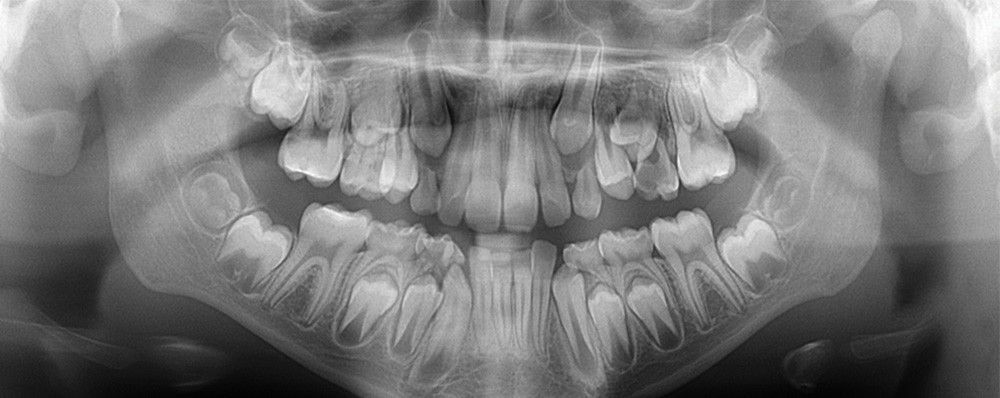

Желаемая область съёмки выбрать интуитивно, при помощи стоматологической карты ORTHOselect. Пользователь может выбрать зубы индивидуально или верхнюю и нижнюю челюсть целиком, или ВНЧС, необходимый размер области сканирования установится автоматически на основе произведённого выбора.